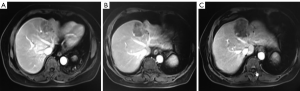

The patient agreed and signed informed consent for publication of her data. This study was carried out in accordance with the Institutional Ethics Committee of Shanghai Tenth People’s Hospital. A 70-year-old woman was transferred to Shanghai Tenth People’s Hospital complaining of right middle abdominal pain. A mass in the distal duodenum was identified after performing a gastroscopy. Pathological examination revealed poorly differentiated duodenal adenocarcinoma (Figure 1). Whole-body positron emission tomography-computed tomography (PET-CT) examination suggested multiple liver metastases (Figure S1), and the patient underwent transcatheter arterial chemoembolization (TACE) for the liver metastases. Therefore, the patient was diagnosed at stage IV. Genetic testing was performed in this patient to predict prognosis and guide clinical management. Next-generation sequencing (NGS) detected 35 gene mutations, small insertions/deletions or gene fusions related to targeted therapy or prognosis (Table S1). single-nucleotide polymorphisms (SNPs) of 13 genes associated with chemotherapy agents were also tested (Table 1). A gene test indicated that the patient was sensitive to oxaliplatin and fluorouracil. Based on the gene detection results and our experience, we treated her with palliative chemotherapy with two courses of XELOX (oxaliplatin 130 mg/m2 d1 + capecitabine 1 g/m2 d1–14 q3w). Tumor assessment by MRI showed stable disease. However, tumor markers (CA724: 42.86) were elevated. Therefore, using this information in conjunction with our experience in CRC, the patient was treated with XELOX plus bevacizumab (7.5 mg/kg) combination therapy. After 6 cycles of treatment, the patient disease status was stable with good tolerance of this regimen. Therefore, we continued this regimen as maintenance therapy with a longer treatment interval (every 4–6 weeks). Considering the neurotoxicity of oxaliplatin, stop and go policy was applied with oxaliplatin removed from cycle 16 to cycle 30 and added again in the next 10 cycles. After 20 courses of regimens (January 24, 2013 to June 18, 2014), the CA724 tumor marker decreased and was stable with continued treatment until disease progression (Figure 2). The treatment was well-tolerated with limited adverse effects. Totally, the patient underwent 40 cycles XELOX plus bevacizumab using stop and go policy for more than 3 years with stable disease from January 24, 2013 to November 24, 2016. The patient experienced Grade 3 proteinuria and Grade 2 neurotoxicity. An MRI scan on January 9, 2017 revealed disease progression of the liver lesions (Figure 3). Therefore, the patient received two courses of bevacizumab plus tegafur, gimeracil, and oteracil potassium capsules (50 mg BID d1–14) with irinotecan (180 mg/m2). She then underwent one course of high-intensity focused ultrasound (HIFU) therapy for the liver lesions. As shown in Table S1, no KRAS or BRAF mutations were detected, and therefore, the patient received targeted therapy with cetuximab (500 mg/m2 q3w) combined with irinotecan with a PFS of 10 months. However, the patient progressed again in January 2018. She was then treated with regorafenib, which is a third-line treatment option for patients with metastatic colorectal cancer. The patient died three months later because of a heart attack.